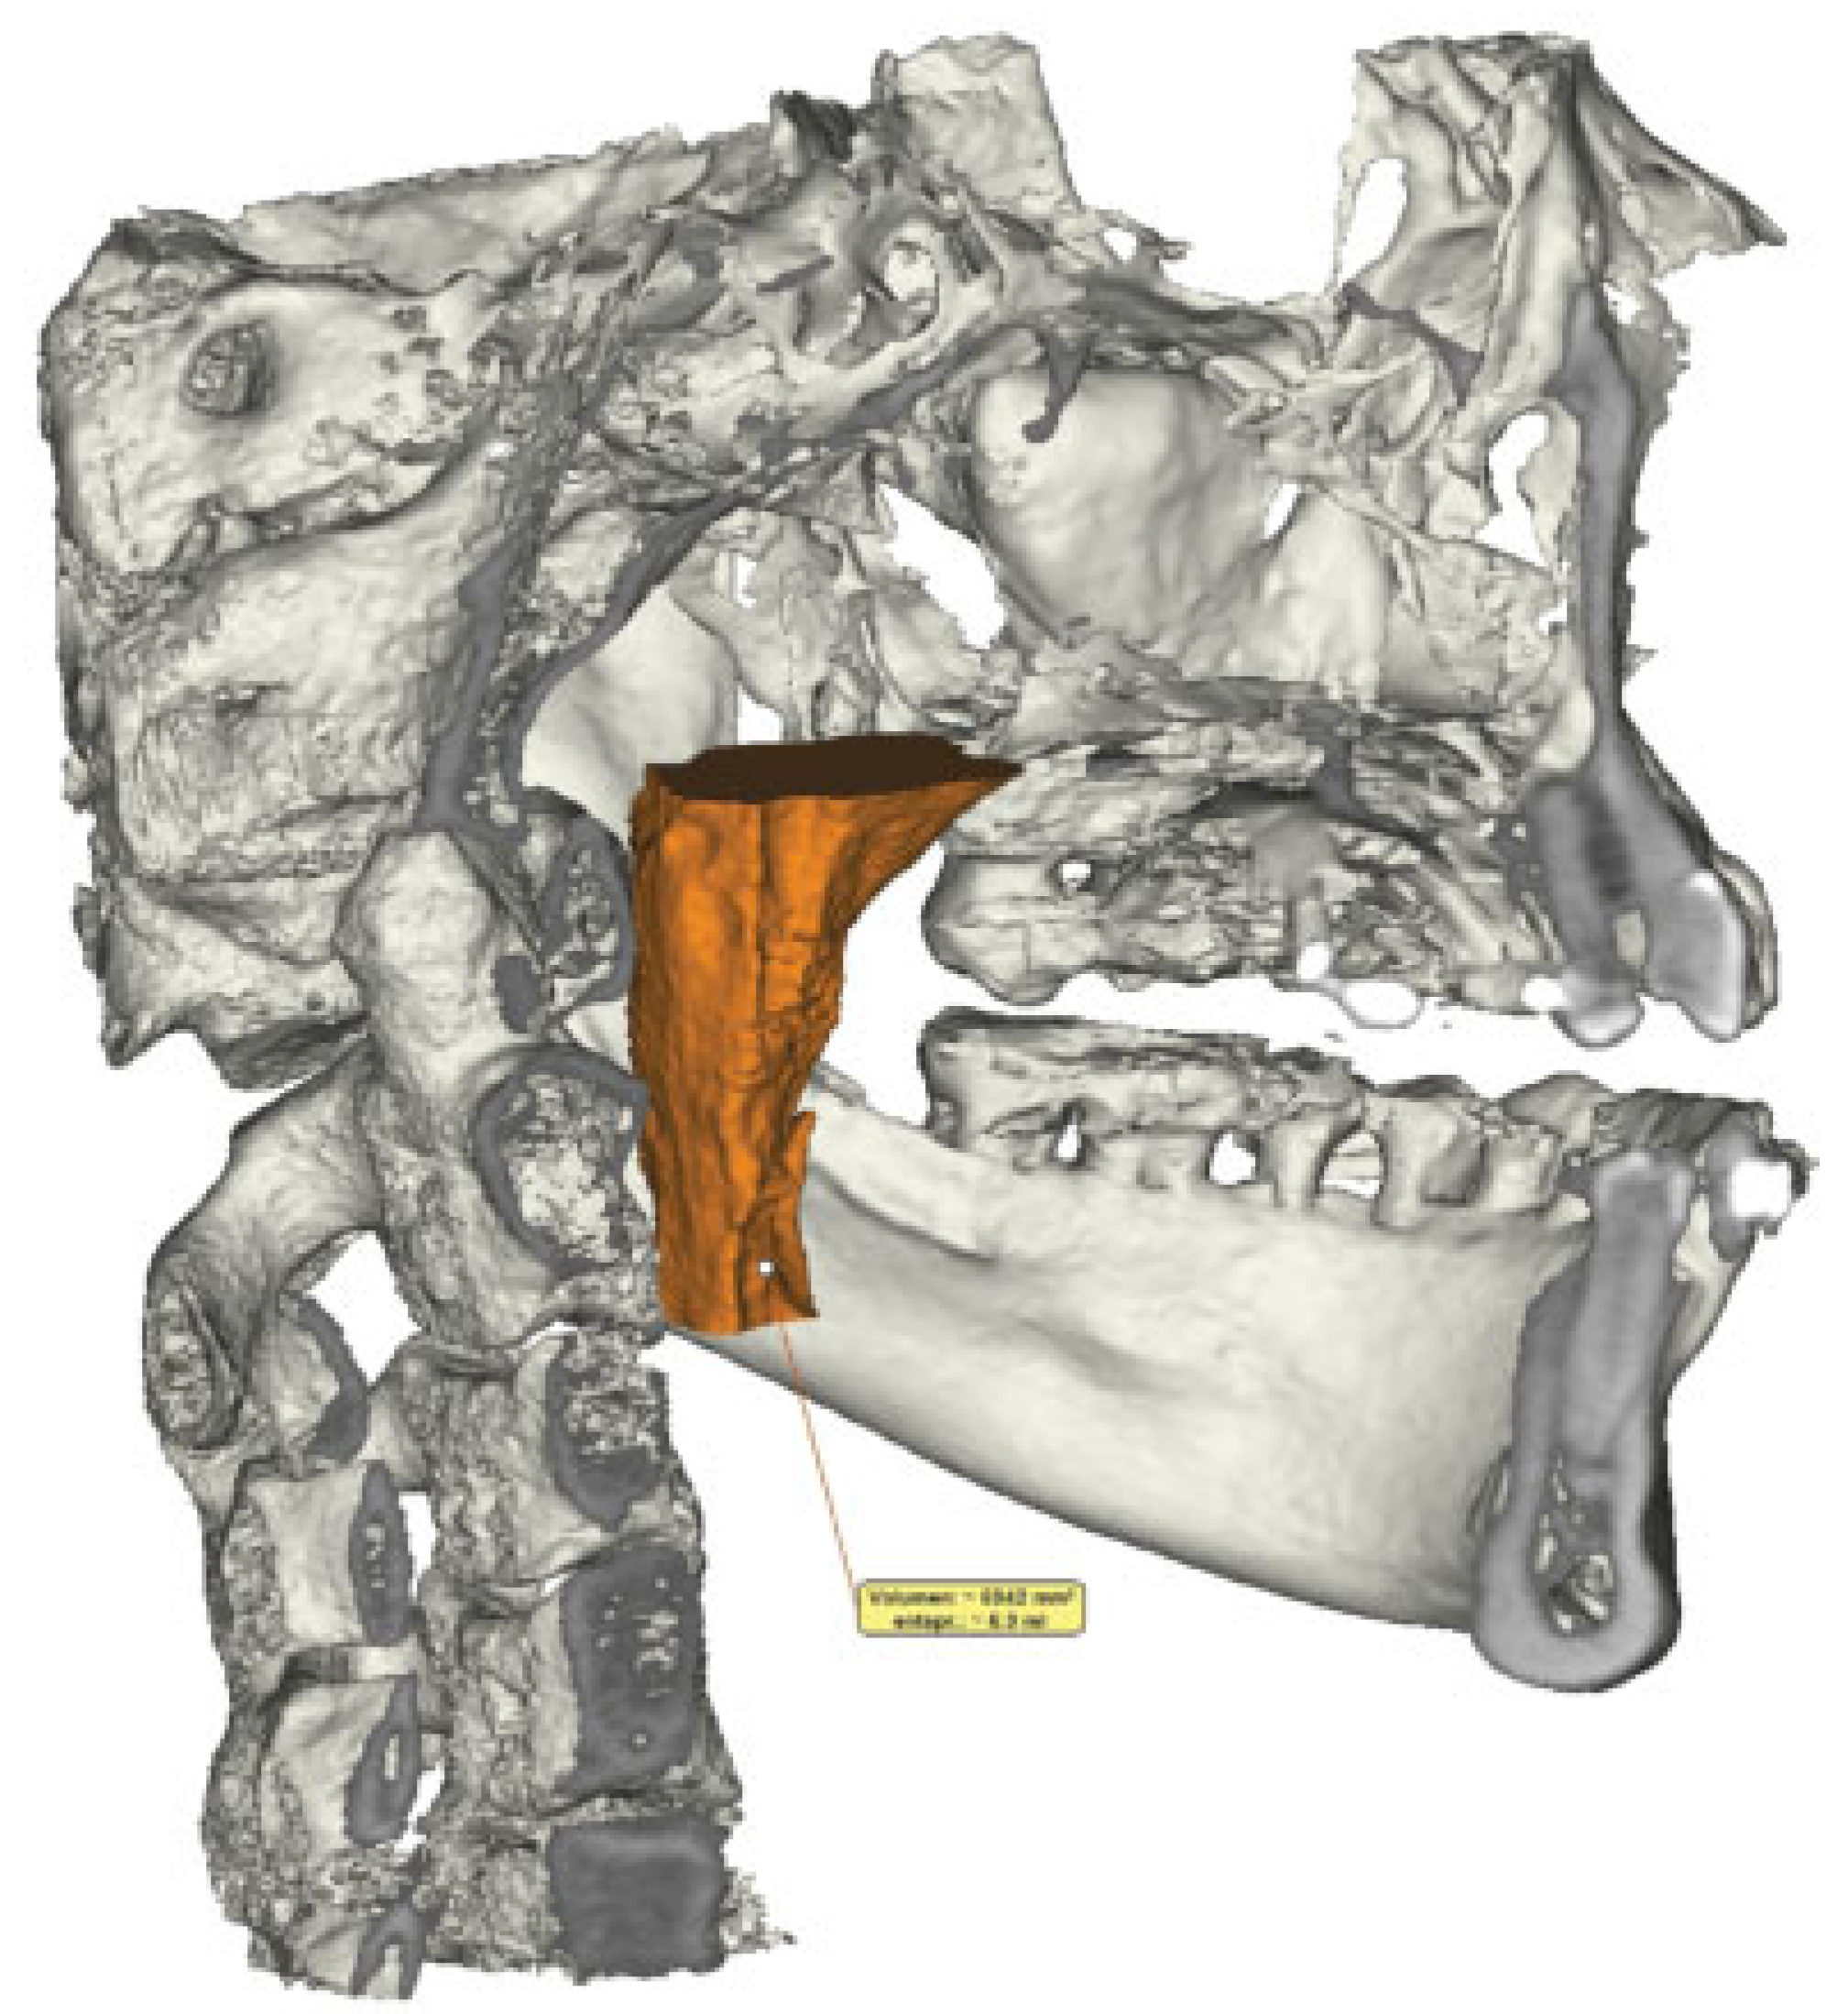

Comparison of Imaging Softwares for Upper Airway Evaluation: Preliminary Study

:Materials and Methods

Results